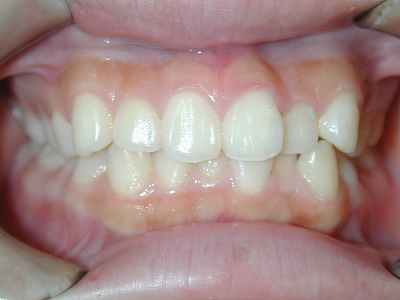

常滑市小林町在住 S.T様(15歳女性)

S.T様は下顎前歯の叢生が主訴でお母様と無料矯正相談で来院されました。

口を閉じる際に口元の緊張があり、横顔に突出感がありました。

以前に上顎前歯の部分矯正をされたご経験があるとお話しされておりました。

そのためか上顎犬歯の横幅(幅径)が通常より少なく思いました。

試料採取より診断の結果、上顎の前歯にも軽度の叢生があり、口元の緊張を改善し、

前歯の叢生の治療のために抜歯が必要であることを説明し、了承が得られたので本格矯正で治療をすすめることとなりました。

上顎前歯に軽度の叢生、下顎前歯に叢生がみられます前歯の上下の接触状態が緊密でなく軽度の舌癖の存在を疑います。

臼歯部は1歯 対 2歯で咬んでいます。